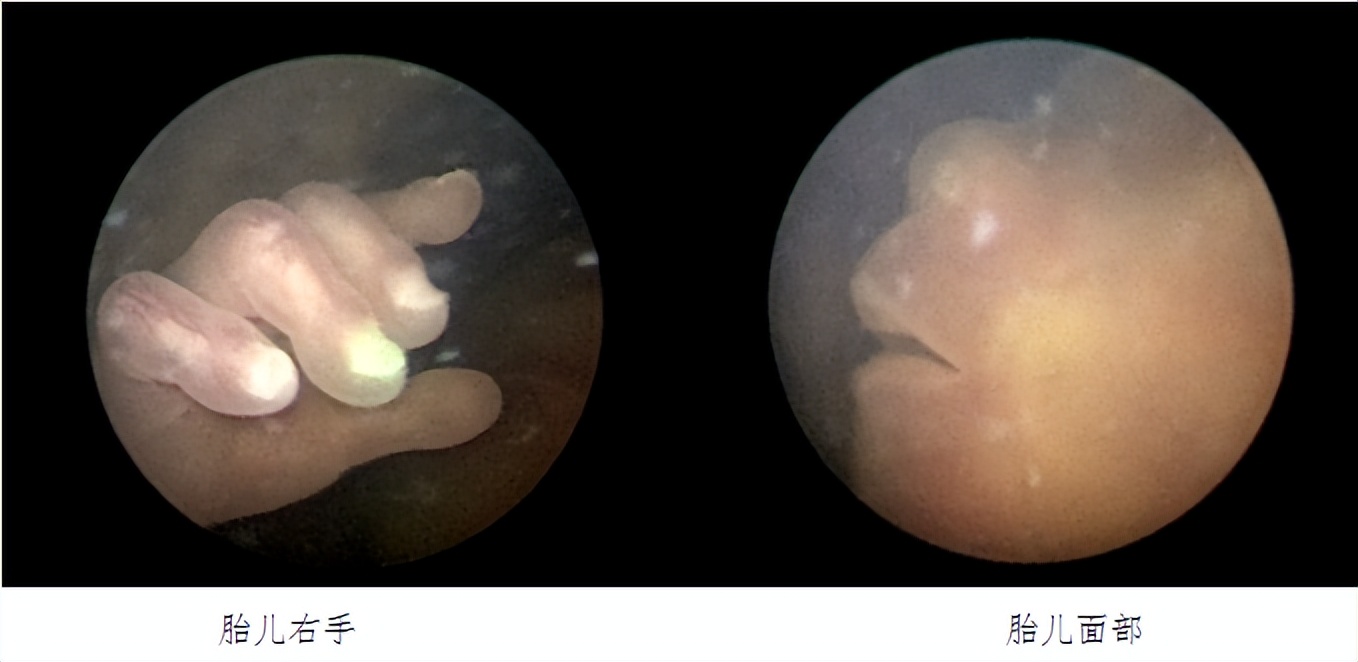

经过充分沟通与讨论,郑女士决定进行胎儿镜手术治疗。医院积极进行术前准备,超声定位确定穿刺路径。手术当天,手术团队成功完成胎儿镜下胎盘交通血管激光凝固术,手术过程顺利。

据悉,双胎输血综合征是双羊膜囊单绒毛膜单卵双胎的严重并发症。通过胎盘间的动-静脉吻合支,血液从动脉向静脉单向分流,使一个胎儿成为供血儿,另一个胎儿成为受血儿,造成供血儿贫血,血容量减少,致使生长受限,肾灌注不足,羊水过少,甚至营养不良而死亡;受血儿血容量增加,动脉压增高,各器官体积增大,胎儿体重增加,可发生充血型心力衰竭,胎儿水肿,羊水过多。胎儿镜手术可通过直径仅2mm的内窥镜,伸入孕妈妈子宫、羊水内,清楚找到双胎间隔膜以及隔膜两旁的动静脉吻合血管,激光电凝血管达到治疗目的。

胎儿镜下胎盘交通血管激光凝固术